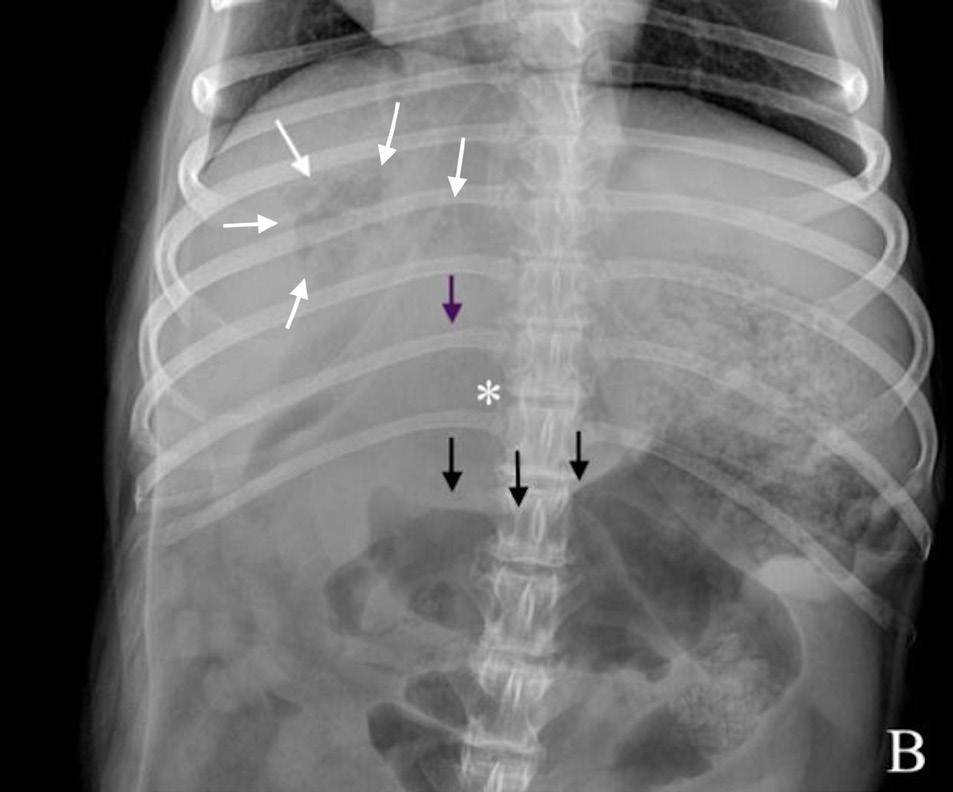

Se realizó un estudio radiográfico de abdomen con proyecciones lateral izquierda y ventrodorsal (Fig. 1).

Figura 1. Radiografías de abdomen de un perro mestizo de 12 años en proyección lateral izquierda (A) y proyección ventrodorsal (B).

Describe las alteraciones radiográficas observadas

Se observa una disminución de la visualización de las serosas abdominales en el abdomen craneal y medio (Fig. 2), con presencia de pequeñas burbujas de gas libre caudoventral a la silueta hepática compatible con neumoperitoneo (Fig. 2A). Ambas proyecciones mostraban una hepatomegalia con bordes redondeados excediendo levemente el arco costal, con presencia de una zona de opacidad gas, de morfología y bordes irregulares, poco definidos, localizada en la zona de proyección hepática en su aspecto craneoventral y con lateralización hacia la derecha (Fig. 2). Así mismo, se apreció otra lesión, de opacidad gas y de menor tamaño, caudalmente a la previamente descrita, en la zona media del hígado y asociada a un efecto masa en la proyección ventrodorsal, que producía hacia caudal un desplazamiento del cuerpo gástrico y antro pilórico (Fig. 2B). Como hallazgo incidental, se observó una espondilosis ventrolateral deformante en la columna lumbar.

¿Cuáles son los diagnósticos diferenciales compatibles con los signos radiográficos observados?

La pérdida de diferenciación de serosas fue compatible con un leve volumen de líquido libre abdominal o inflamación peritoneal, sin poder descartar otras causas como una carcinomatosis/sarcomatosis peritoneal. Las causas más comunes de neumoperitoneo incluyen heridas penetrantes, fuga de gas de órganos enfisematosos, perforación o rotura de órganos que contienen gas debido a traumatismos, neoplasias o ulceraciones y por causas iatrogénicas, (p. ej., laparotomías).1 La lesión localizada en la proyección hepática más cranealmente y lateralizada hacia la derecha con contenido gas, según su localización, podría ser compatible con un absceso hepático, colecistitis enfisematosa, neoplasia o granuloma hepático infectado. La lesión localizada más caudalmente y con efecto masa a nivel gástrico podría corresponderse con otro absceso o con la presencia de una masa necrosada de origen benigno (p. ej., hiperplasia nodular, quiste, hematoma) o maligno (p. ej., carcinoma hepatocelular).

Ante el conjunto de los hallazgos radiológicos encontrados, la sospecha principal fue de una rotura de un absceso/neoplasia hepática necrosada.

Figura 2. Imágenes ampliadas de las radiografías en proyección lateral izquierda (A) y ventrodorsal (B). Se observa la lesión de opacidad gas y bordes irregulares localizada en la proyección hepática, en su aspecto craneoventral y lateralizada a la derecha (flechas blancas). Se muestra otra lesión de opacidad gas, de menor tamaño respecto a la descrita, en la zona media del hígado (flechas moradas), que provoca un efecto masa (*) y genera un desplazamiento hacia caudal del antro pilórico y cuerpo gástrico (flechas negras). Caudoventral a la silueta hepática se observan pequeñas burbujas de gas libre compatible con neumoperitoneo (flechas azules).